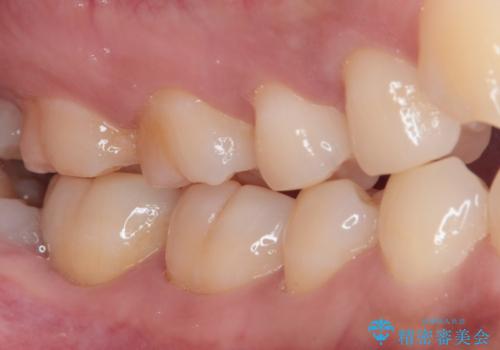

- 親知らず周りに痛みを感じるとのことで来院された患者様です。

レントゲン写真より、埋もれた親知らずの影響で手前の奥歯の歯根近くのところに大きなむし歯があることが分かりました。

まずは親知らずを抜歯し、その後手前の歯の処置を行うこととしました。

手前の歯については、痛みなどの症状は認められなかったため、神経を取り除く必要はないと判断されましたが、むし歯の場所が深いため、親知らず抜歯後に歯肉の状態が改善してからオールセラミッククラウンにて補綴治療を行うこととしました。